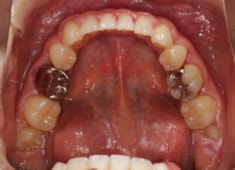

治療開始時